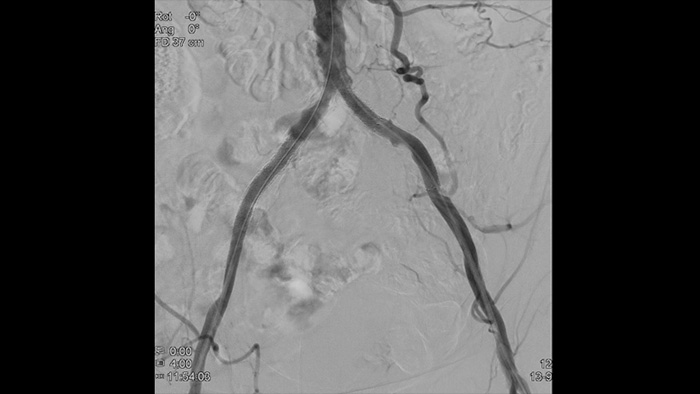

Imágenes de alta definición de los vasos con detalles vasculares superiores para apoyar las estrategias de tratamiento precisas, la navegación y el seguimiento.

Nuestros catéteres para obtener imágenes periféricas ayudan a evaluar la localización de la enfermedad y la morfología de la lesión, incluidos las calcificaciones y los trombos. La EIV también puede utilizarse para dimensionar adecuadamente los stents y confirmar la finalización del tratamiento.